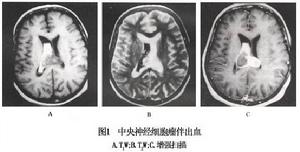

MRI:特徵 性的MRI表現:①好發部位:腫瘤大都位於側腦室前2/3,透明隔或孟氏孔區,典型表現為以廣基底與側腦室透明隔相連的腫瘤,均伴有不同程度腦積水。②形態:腫瘤形態不規則,多呈分葉狀,邊緣呈繩索狀。此為CNC的一個較為特徵性的影像學表現。③邊界:腫瘤邊界清晰,一般不侵入腦實質。④平掃信號改變:腫瘤呈不均勻等長T1 等長T2 混雜信號,其中等T1 等T2 信號代表腫瘤組織,長T1 長T2 信號代表囊變、壞死。有些病變中還可見無信號區,代表鈣化或腫瘤血管。腦室內的信號不一及匍行性流空是CNC的另一特徵性MRI表現。⑤增強掃描信號改變:多呈輕中度強化。

CT掃描見腫瘤位於一側腦室內或位於透明膈在腦室內邊界清楚呈圓形等密度或略高而不均勻密度影半數以上腫瘤有點狀鈣化,當鈣化灶較大時X線平片也可見到。幕上中樞神經細胞瘤增強後腫瘤有中度至明顯強化MRI成像優於CT,對腫瘤範圍及所處部位有診斷價值可見多數腫瘤與透明隔或側腦室壁有關。腫瘤實質部分T1W為等或稍高信號,T2W為高信號,瘤內可見血管流空影。部分腫瘤常伴有出血靜脈注入順磁性顯影劑後,可見輕度增強腫瘤與側腦室壁或透明膈相附著(圖1)。